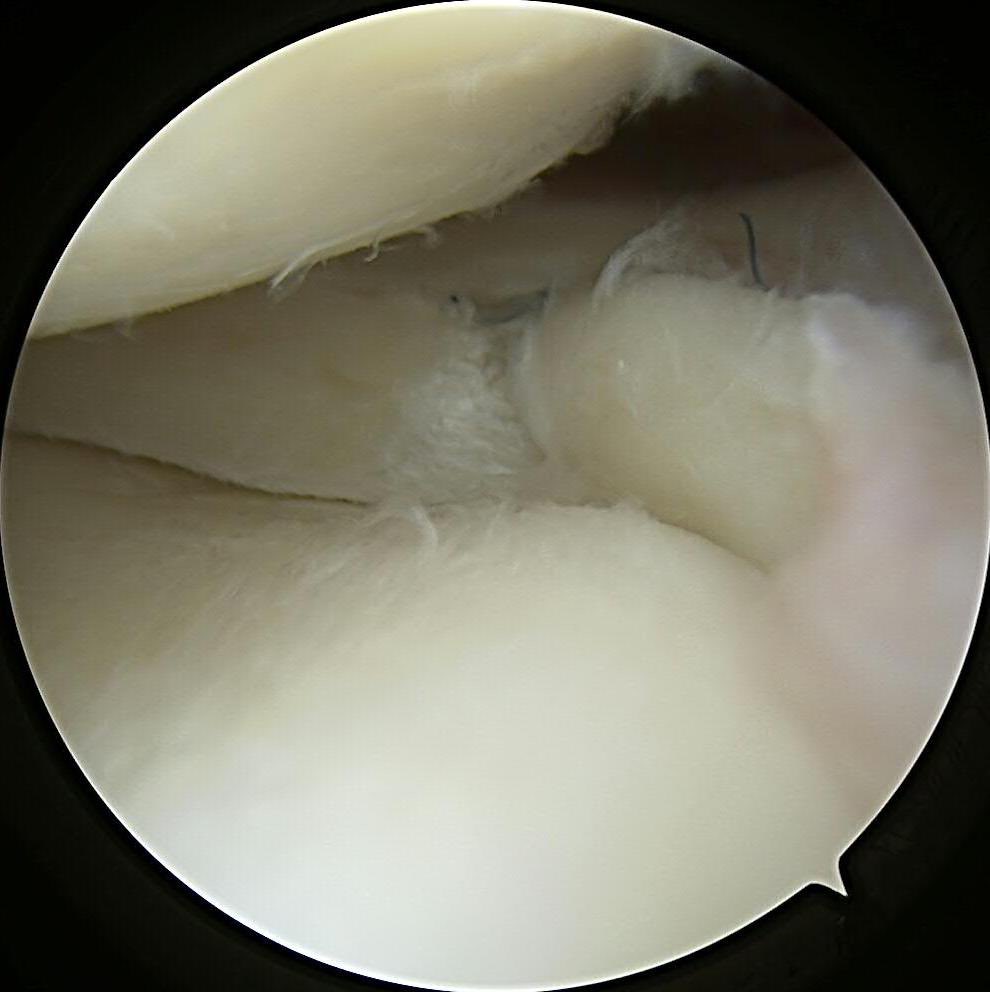

#savethemeniscus LMORT: Lateral Meniscus Oblique Radial Tear- often seen with an acute ACL injury. REPAIR or RESECT?